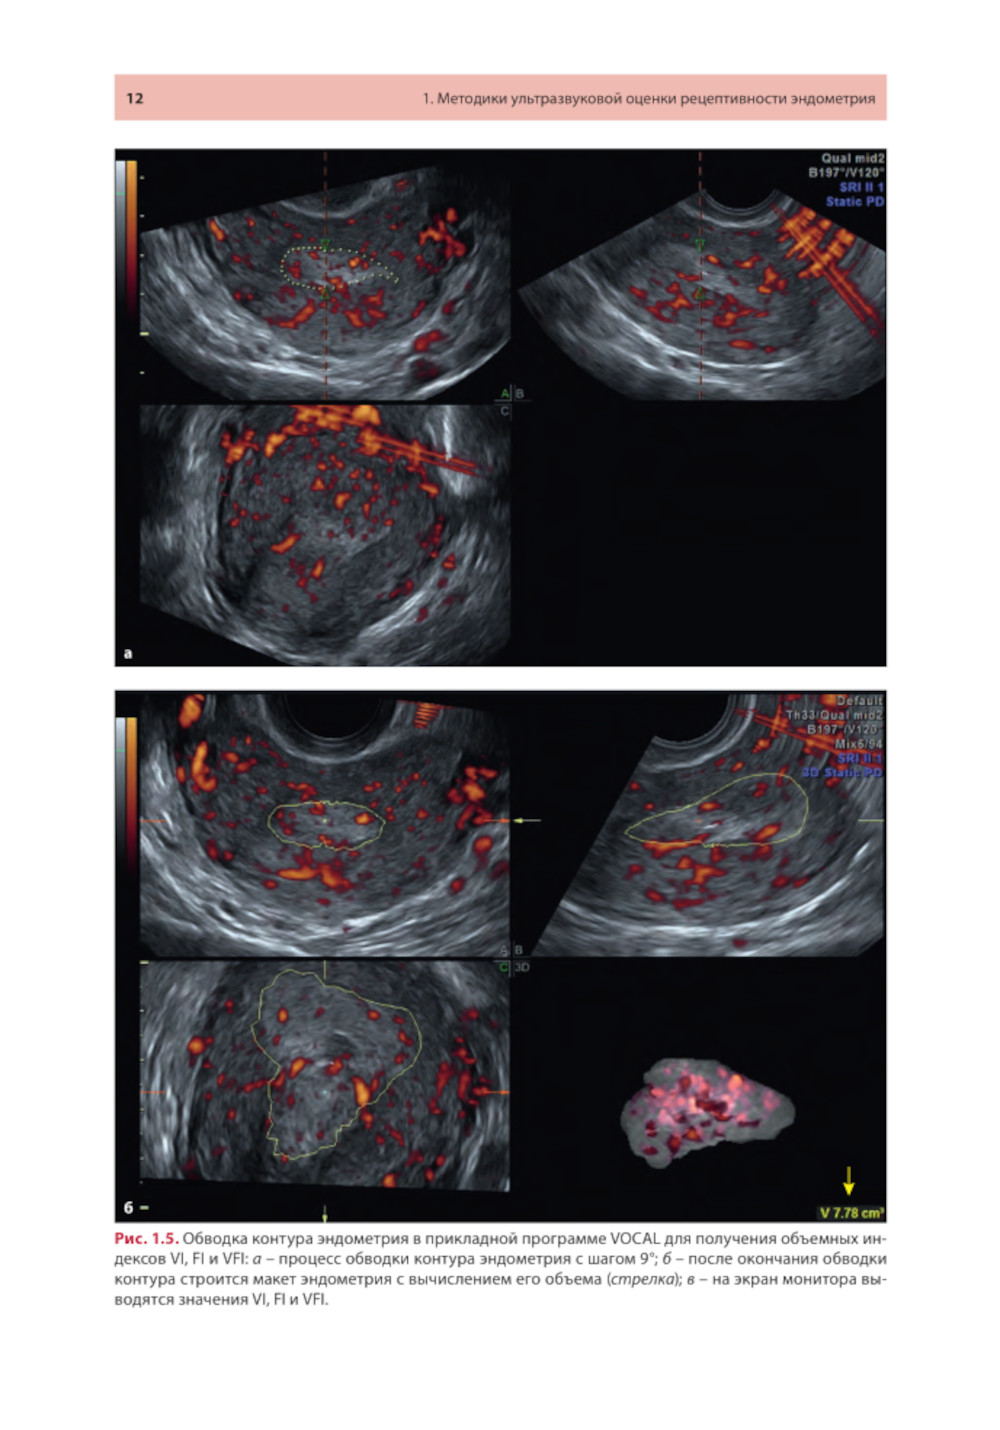

Методические рекомендации освещают современное состояние проблемы ультразвуковой оценки рецептивности эндометрия от общепринятых маркеров до малоизученных, в том числе перспективных, направлений. Описаны ультразвуковые методики, позволяющие оценивать признаки рецептивности в 2D- и 3D-режимах с акцентом на ошибках, которые влияют на интерпретацию результатов. Представлены различные шкалы комплексного анализа. Утверждено в качестве методических рекомендаций для проведения циклов тематического усовершенствования «Ультразвуковая диагностика в гинекологии», общего усовершенствования, ординаторов и аспирантов, проходящих обучение по направлению «Ультразвуковая диагностика, акушерство и гинекология, репродуктология». Протокол Ученого совета ФНМО МИ ФГАОУ ВО РУДН №5 от 16.05.2023.| Издательство | МЕДпресс-информ |